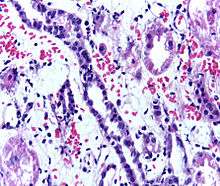

Presence of lymphocytes within the tubular epithelium, attesting to acute cellular rejection of a renal graft. Biopsy sample.

Problems after a transplant may include: Post operative complication, bleeding, infection, vascular thrombosis and urinary complications